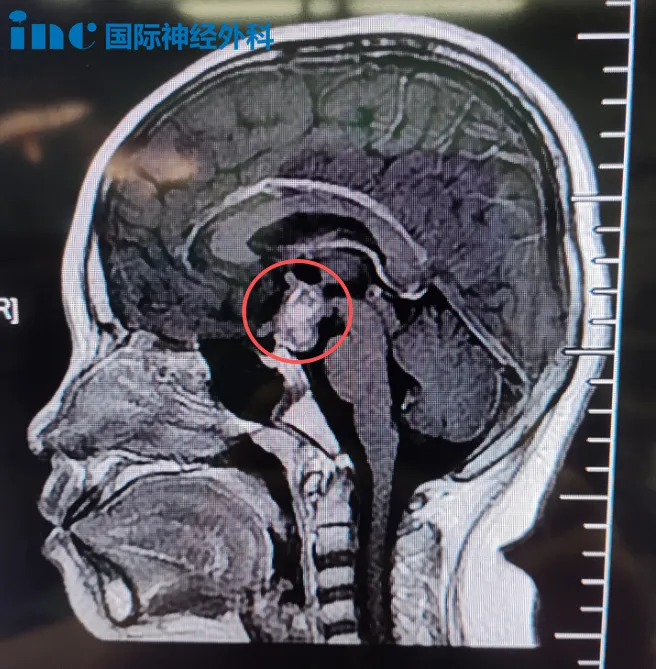

在患儿颅内,一个具有侵袭特性的病变——颅咽管瘤,正潜在影响其未来发展。

该台被巴特朗菲教授称为"不容易"的手术主要难点在于:

肿瘤起源于垂体柄内部,垂体柄类似包裹在外部的薄环结构,非常纤细且脆弱。垂体柄被肿瘤扩张呈气球样形态,手术需切开小口,取出"气球"内部肿瘤,同时保留外部这层薄弱垂体柄结构。这不仅需要精细显微操作技术,还需特殊手术技巧——既要最大限度切除肿瘤,又要极大程度保留极其细小的垂体柄结构。

最终,巴特朗菲教授主刀完成手术,垂体柄成功保留,肿瘤切除结果满意。